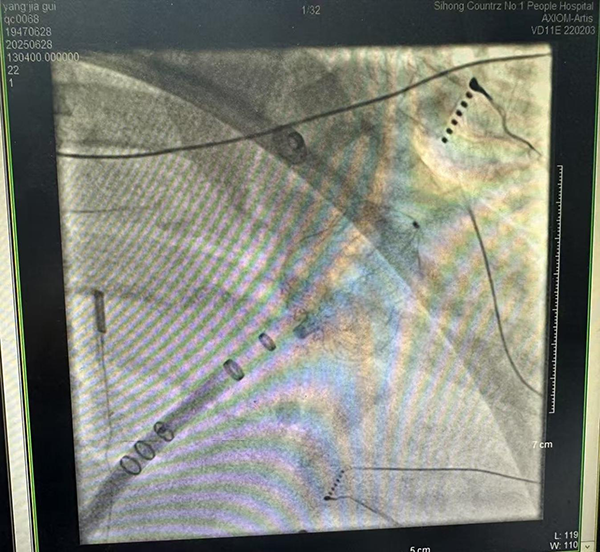

患者楊大爺(化名)罹患房顫多年,長期飽受心悸、心衰與卒中威脅,50天前因心源性腦梗死導(dǎo)致右側(cè)肢體肌力下降到泗洪分院就診,經(jīng)過積極抗凝及改善心功能治療,并在徐醫(yī)附院專家指導(dǎo)下聯(lián)合制定治療方案,心血管內(nèi)科、麻醉科、超聲科、影像科等多學(xué)科團隊深入討論,排除手術(shù)禁忌證,認真制定手術(shù)方案及應(yīng)急預(yù)案,并與患者家屬充分溝通后,于6月28日在全身麻醉下,成功實施了在心腔內(nèi)超聲導(dǎo)管(ICE)引導(dǎo)下的“一站式”手術(shù),歷時4.5小時。

傳統(tǒng)治療中,房顫患者需分階段解決心律失常和血栓預(yù)防問題。此次開展的“一站式”手術(shù)創(chuàng)新性融合兩項關(guān)鍵技術(shù):1.射頻消融術(shù):通過導(dǎo)管精準(zhǔn)阻斷異常電信號,恢復(fù)正常心律;2.左心耳封堵術(shù):封堵房顫患者血栓最易形成的左心耳,顯著降低卒中風(fēng)險達90%以上。手術(shù)僅需股靜脈穿刺,創(chuàng)傷小、恢復(fù)快,為高齡、高卒中風(fēng)險患者提供了更安全有效的治療選擇。